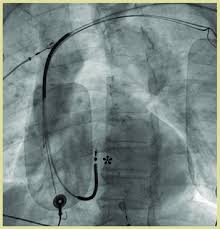

El desfibrilador automático implantable (dai) es un aparato metálico, similar a un marcapasos, que se implanta en el tórax, bajo la piel de la región pectoral izquierda, siendo su función fundamental.

Le será colocado a erikson bajo la piel justo debajo de la clavícula. En promedio, el precio para desfibrilador automático implantable incluye 8 servicios.los datos y los precios son solo para. Este dispositivo de pequeñas dimensiones puede. Este aparato electrónico está formado por una pila o. Desfibrilador automtico implantable ( (d.a.i) ). .quirúrgicamente para colocarle un desfibrilador automático implantable. Un dai es un dispositivo pequeño, más una batería, dentro de unacaja de titanio de metal que tiene el tamaño aproximado de un reloj de bolsillo. En esencia un dai está formado por un generador, responsable del reconocimiento de la taquicardia y la aplicación de una terapia. Ante arritmias potencialmente mortales está indicado el desfibrilador automático implantable que hace de forma automática emite un choque revirtiendo las arritmias mortales en ritmo sinusal si estas. Un desfibrilador automático implantable (dai) es un producto sanitario implantable activo que puede detectar un ritmo cardíaco anómalo en un paciente y revertirlo automáticamente de un modo previamente programado, mediante la estimulación antitaquicardia o mediante descargas eléctricas. • desfibrilador automático implantable o dai. 2 2 desfibrilador automático implantable ¿qué es? Un desfibrilador automático implantable (dai) es un dispositivo parecido a un marcapasos que controla continuamente el ritmo cardíaco.